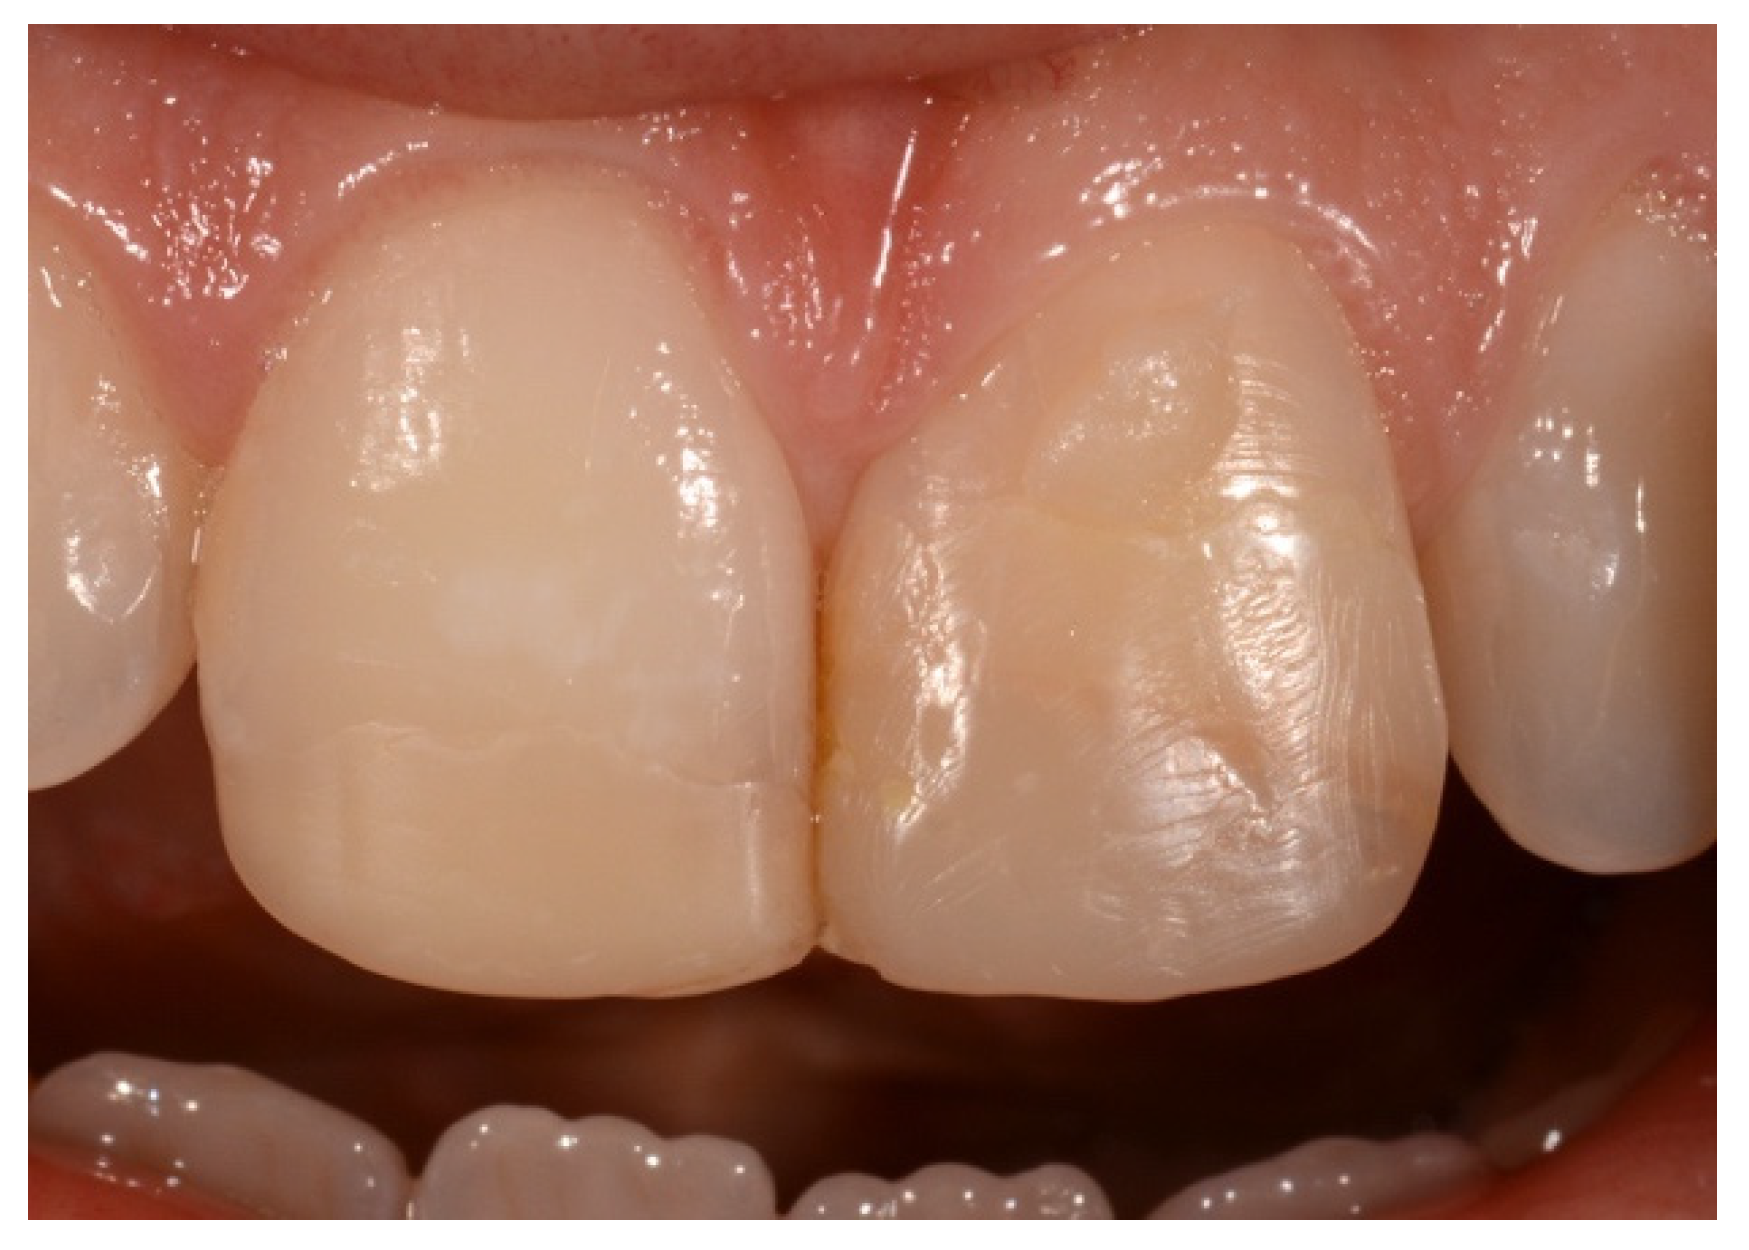

2. Case Presentation